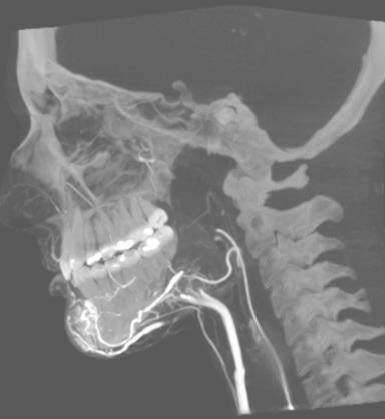

目前神经内科神经介入团队运用DSA手术室常规开展脑卒中急救技术,比如:DSA全脑血管造影术、动脉溶栓、取栓术、(颈动脉、椎动脉、锁骨下动脉)血管成形支架置入术。